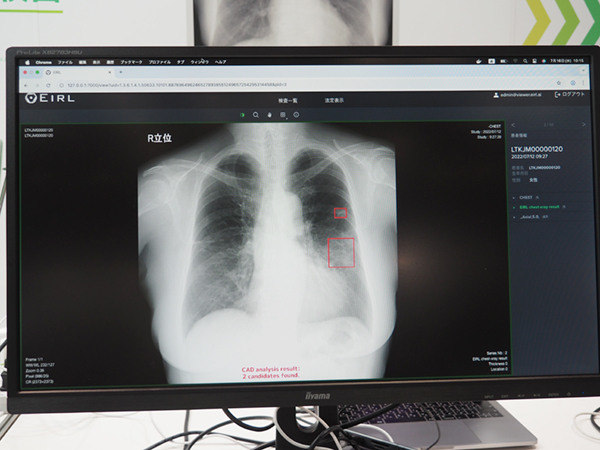

胸部X線画像から異常陰影の候補点を検出する「EIRL Chest Screening」は,4所見(結節影,浸潤影,間質性陰影,無気肺)または肺結節のみを検出することができ,加えて5つの計測(胸腔内の空気含有面積,心胸郭比,縦隔比,大動脈弓の径,肋骨横隔膜角)と過去画像との比較が自動で行われる。日本放射線技術学会が公開しているデータセットを基にした検証では,肺結節の検出精度は,検出が困難な肺結節影(読影難易度1〜5の3)でも感度90.0%の結果を示している。また,自動計測により複数の医師が計測する場合にも計測誤差を抑制できる。過去比較では,経時的変化を画像上に表示する機能を有し,変化の内容(増大や減少)によって□や〇で表示され,一目で把握しやすい。

「EIRL Chest Screening」異常陰影候補の検出結果表示